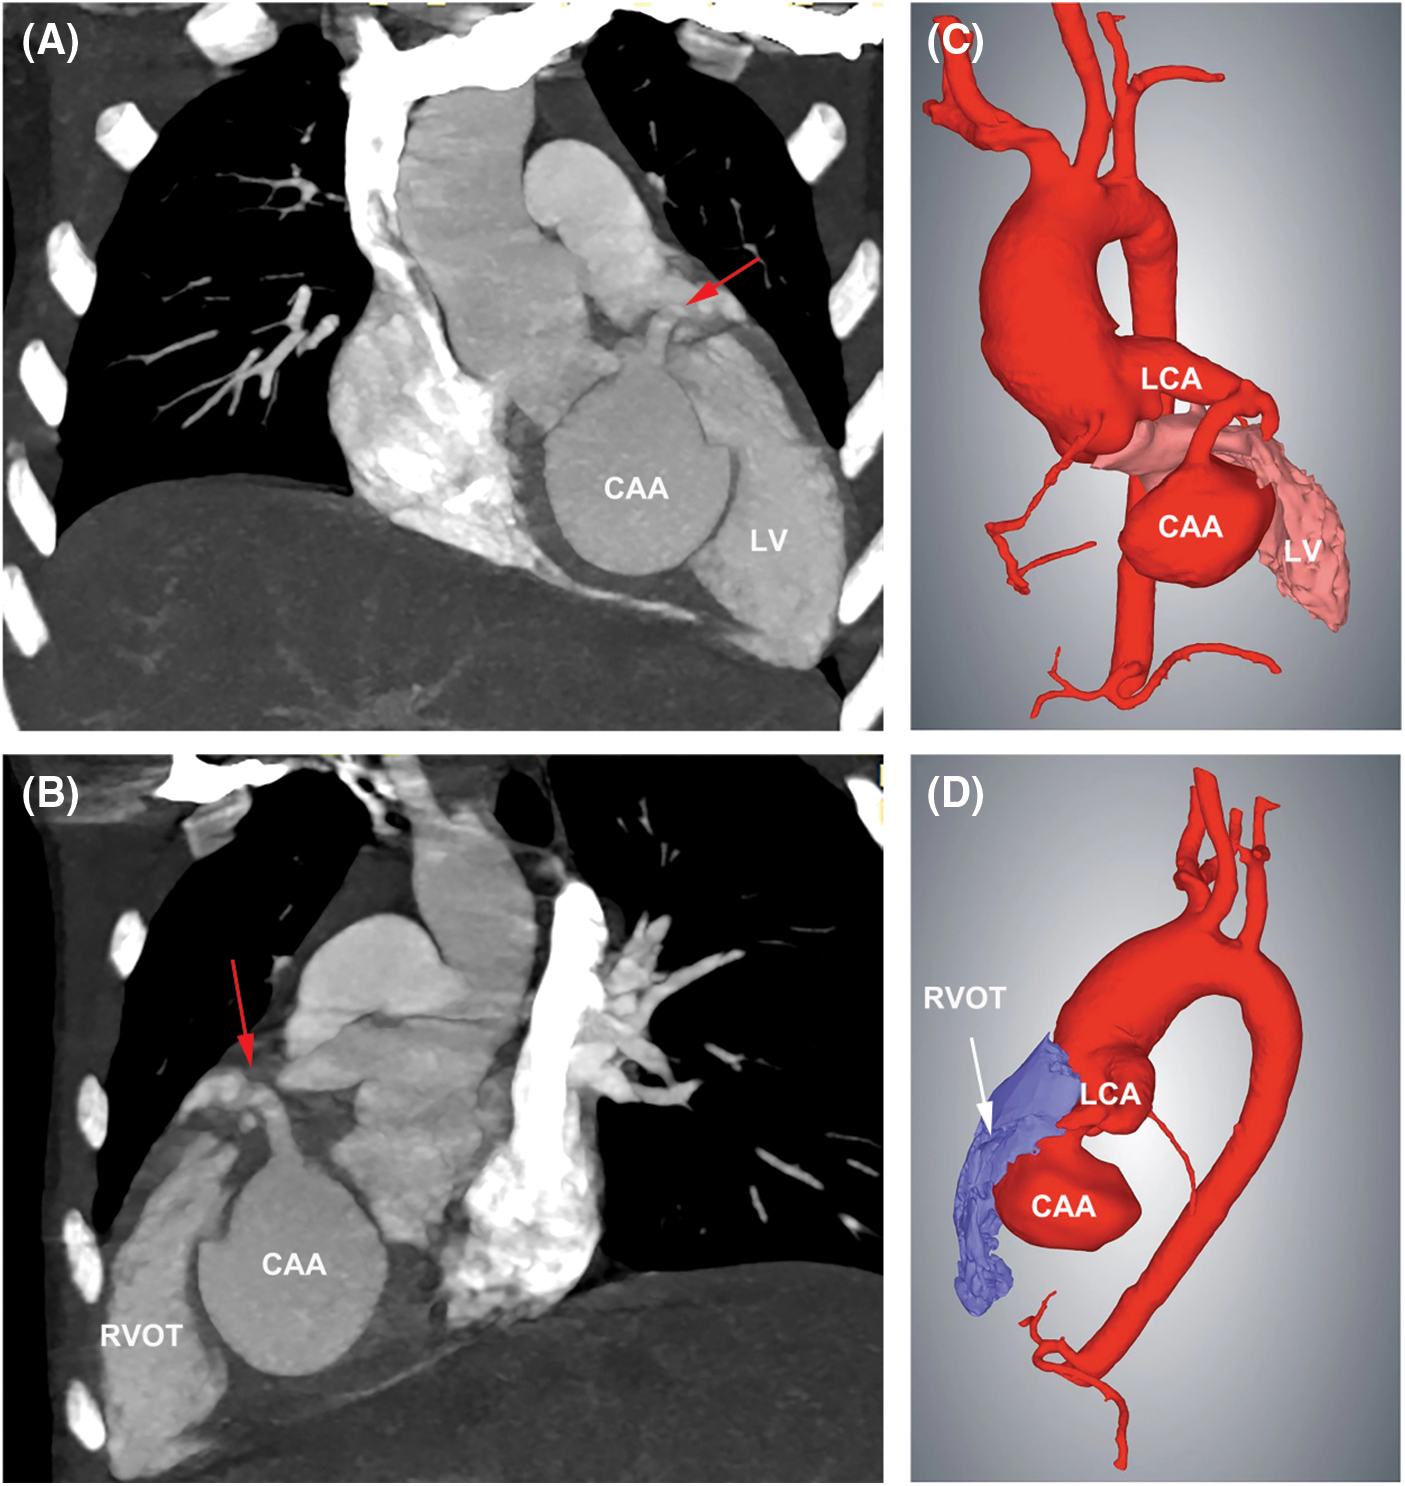

Transthoracic echocardiography (TTE) revealed a severe dilation of the LCA ostium with a giant aneurysmal coronary artery located above the intraventricular septum (IVS) (Figs. 1A and 1B). The coronary artery was draining into LV cavity through an orifice with diameter of 4.0 mm. Color Doppler flow imaging detected a continuous double-phase turbulent spectrum at the orifice, suggesting the presence of an LCA-to-LV fistula (Figs. 1C and 1D). Since no sign of left ventricular overload was present, the shunt was considered small degree. Three-dimensional computed tomography (3D-CT) scan confirmed that the fistula was proximal type, originating from anterior interventricular branch of LCA and draining into LV cavity with giant CAA of 41 mm × 28 mm in diameter (Figs. 2A and 2B). Compression of both LV and right ventricular outflow tract (RVOT) by the giant CAA was seen (Figs. 2C and 2D). If left untreated, the patient would be in danger of aneurysm rupture, thrombus formation in the CAA, and heart failure. Taking all these factors into consideration, and to relieve compression of LV and RVOT, we decided to perform transcatheter closure of both the inlet and outlet of the fistula for the patient.

Figure 2: 3D-CT scan showed the LCA-to-LV fistula with giant CAA. (A) The fistula originated from LCA, and LV compression by the CAA was seen. Red arrow indicated the inlet of the fistula. (B) Compression of RVOT by the CAA was present. Red arrow indicated the inlet of the fistula. (C) 3D Reconstruction confirmed the compression of LV by the CAA. (D) 3D Reconstruction confirmed the compression of RVOT by the CAA